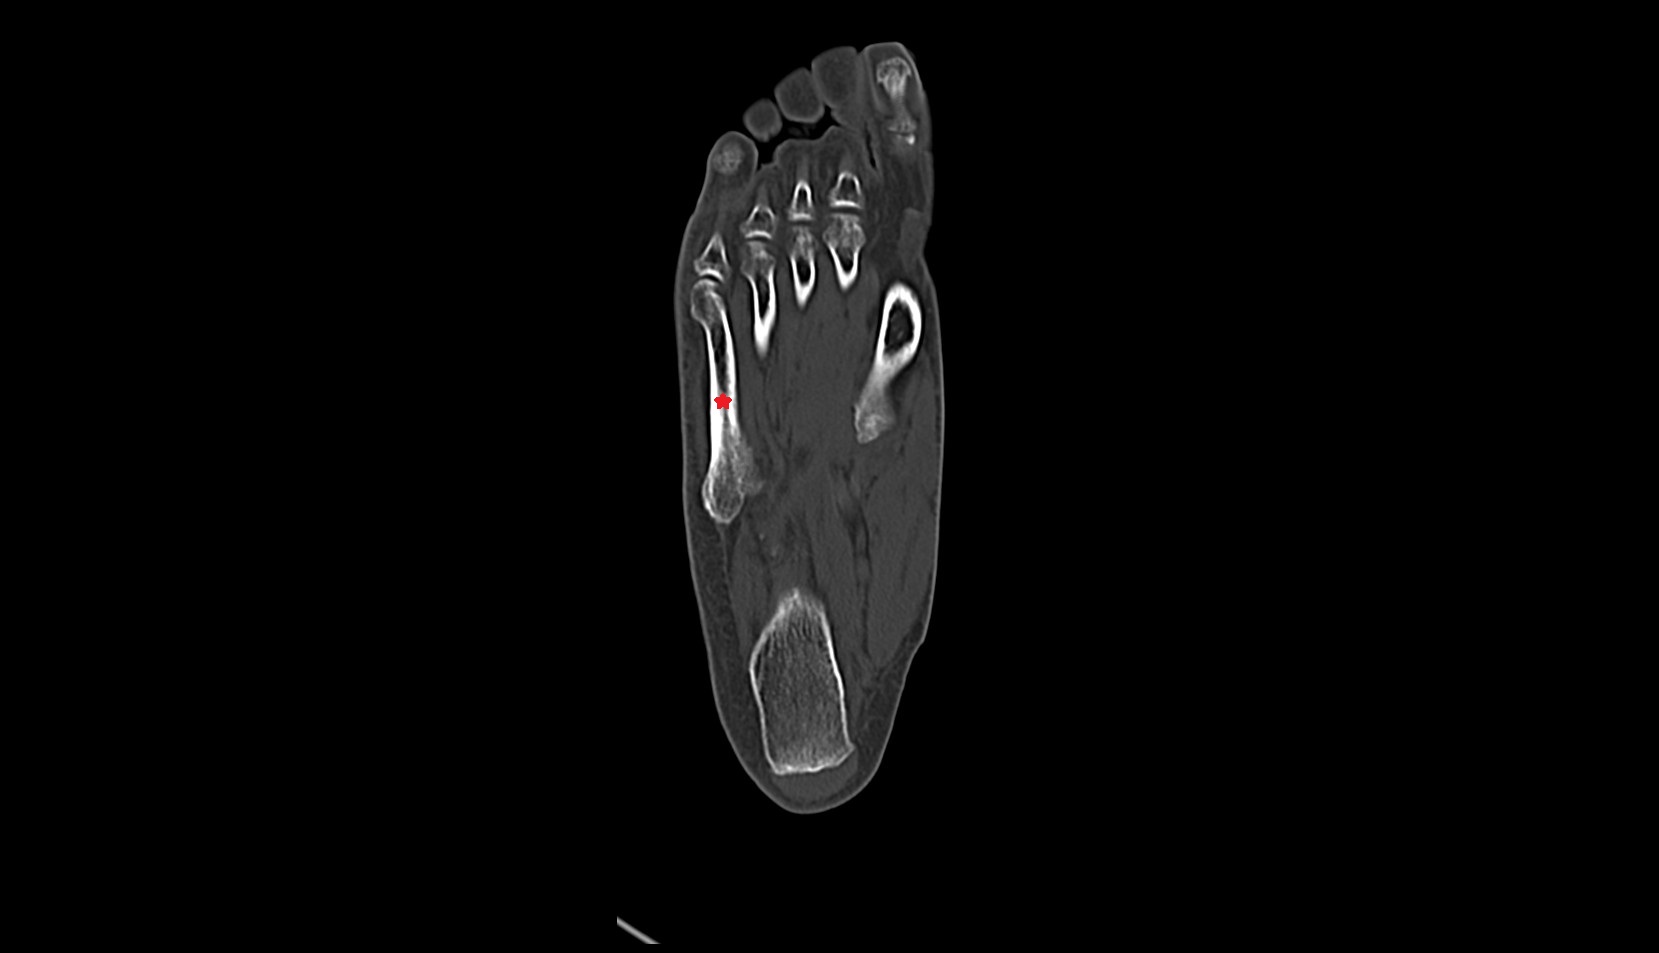

- First metatarsal bone

- Second metatarsal bone

- Third metatarsal bone

- Fourth metatarsal bone

- Fifth metatarsal bone

- Sesamoid bone of great toe

- Lateral sesamoid bone

- Medial sesamoid bone